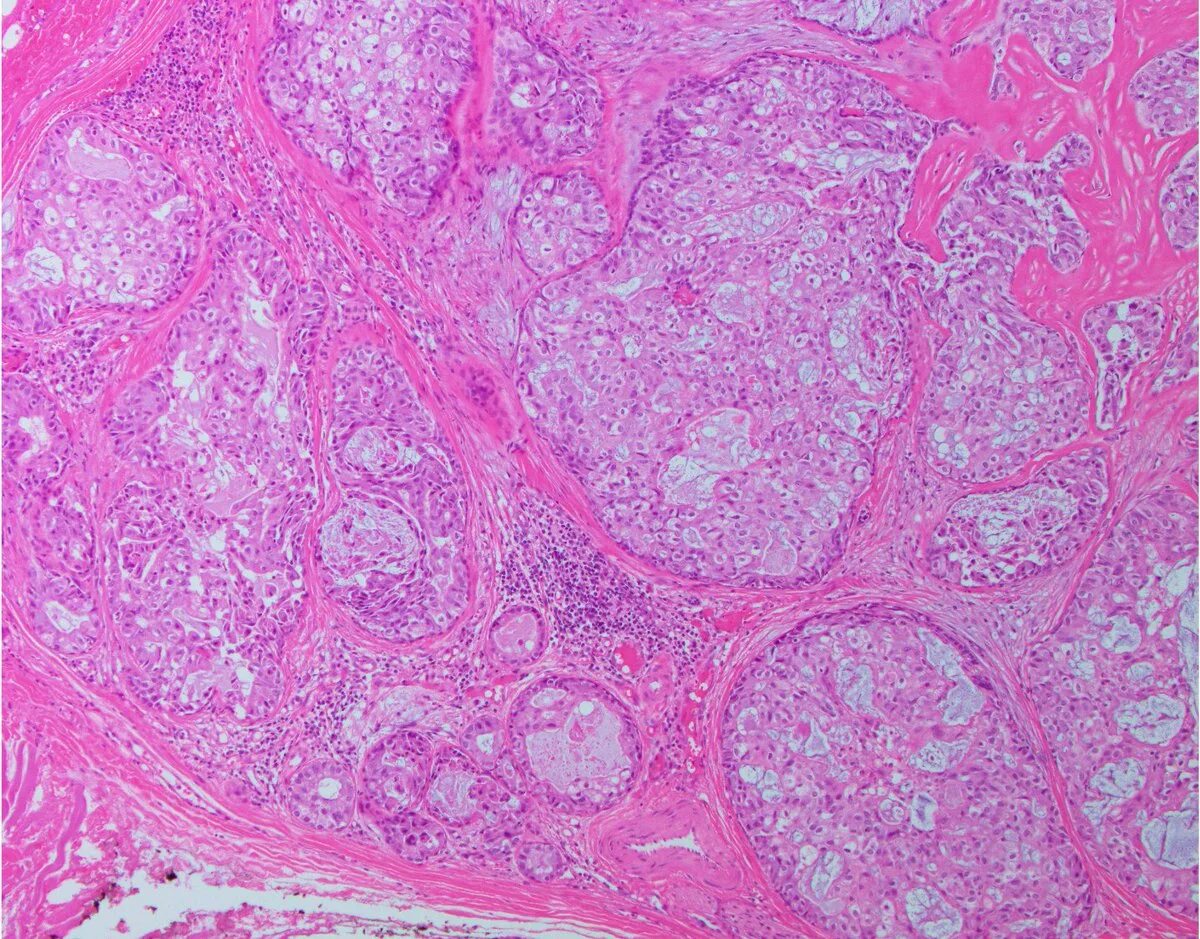

Гистология фото